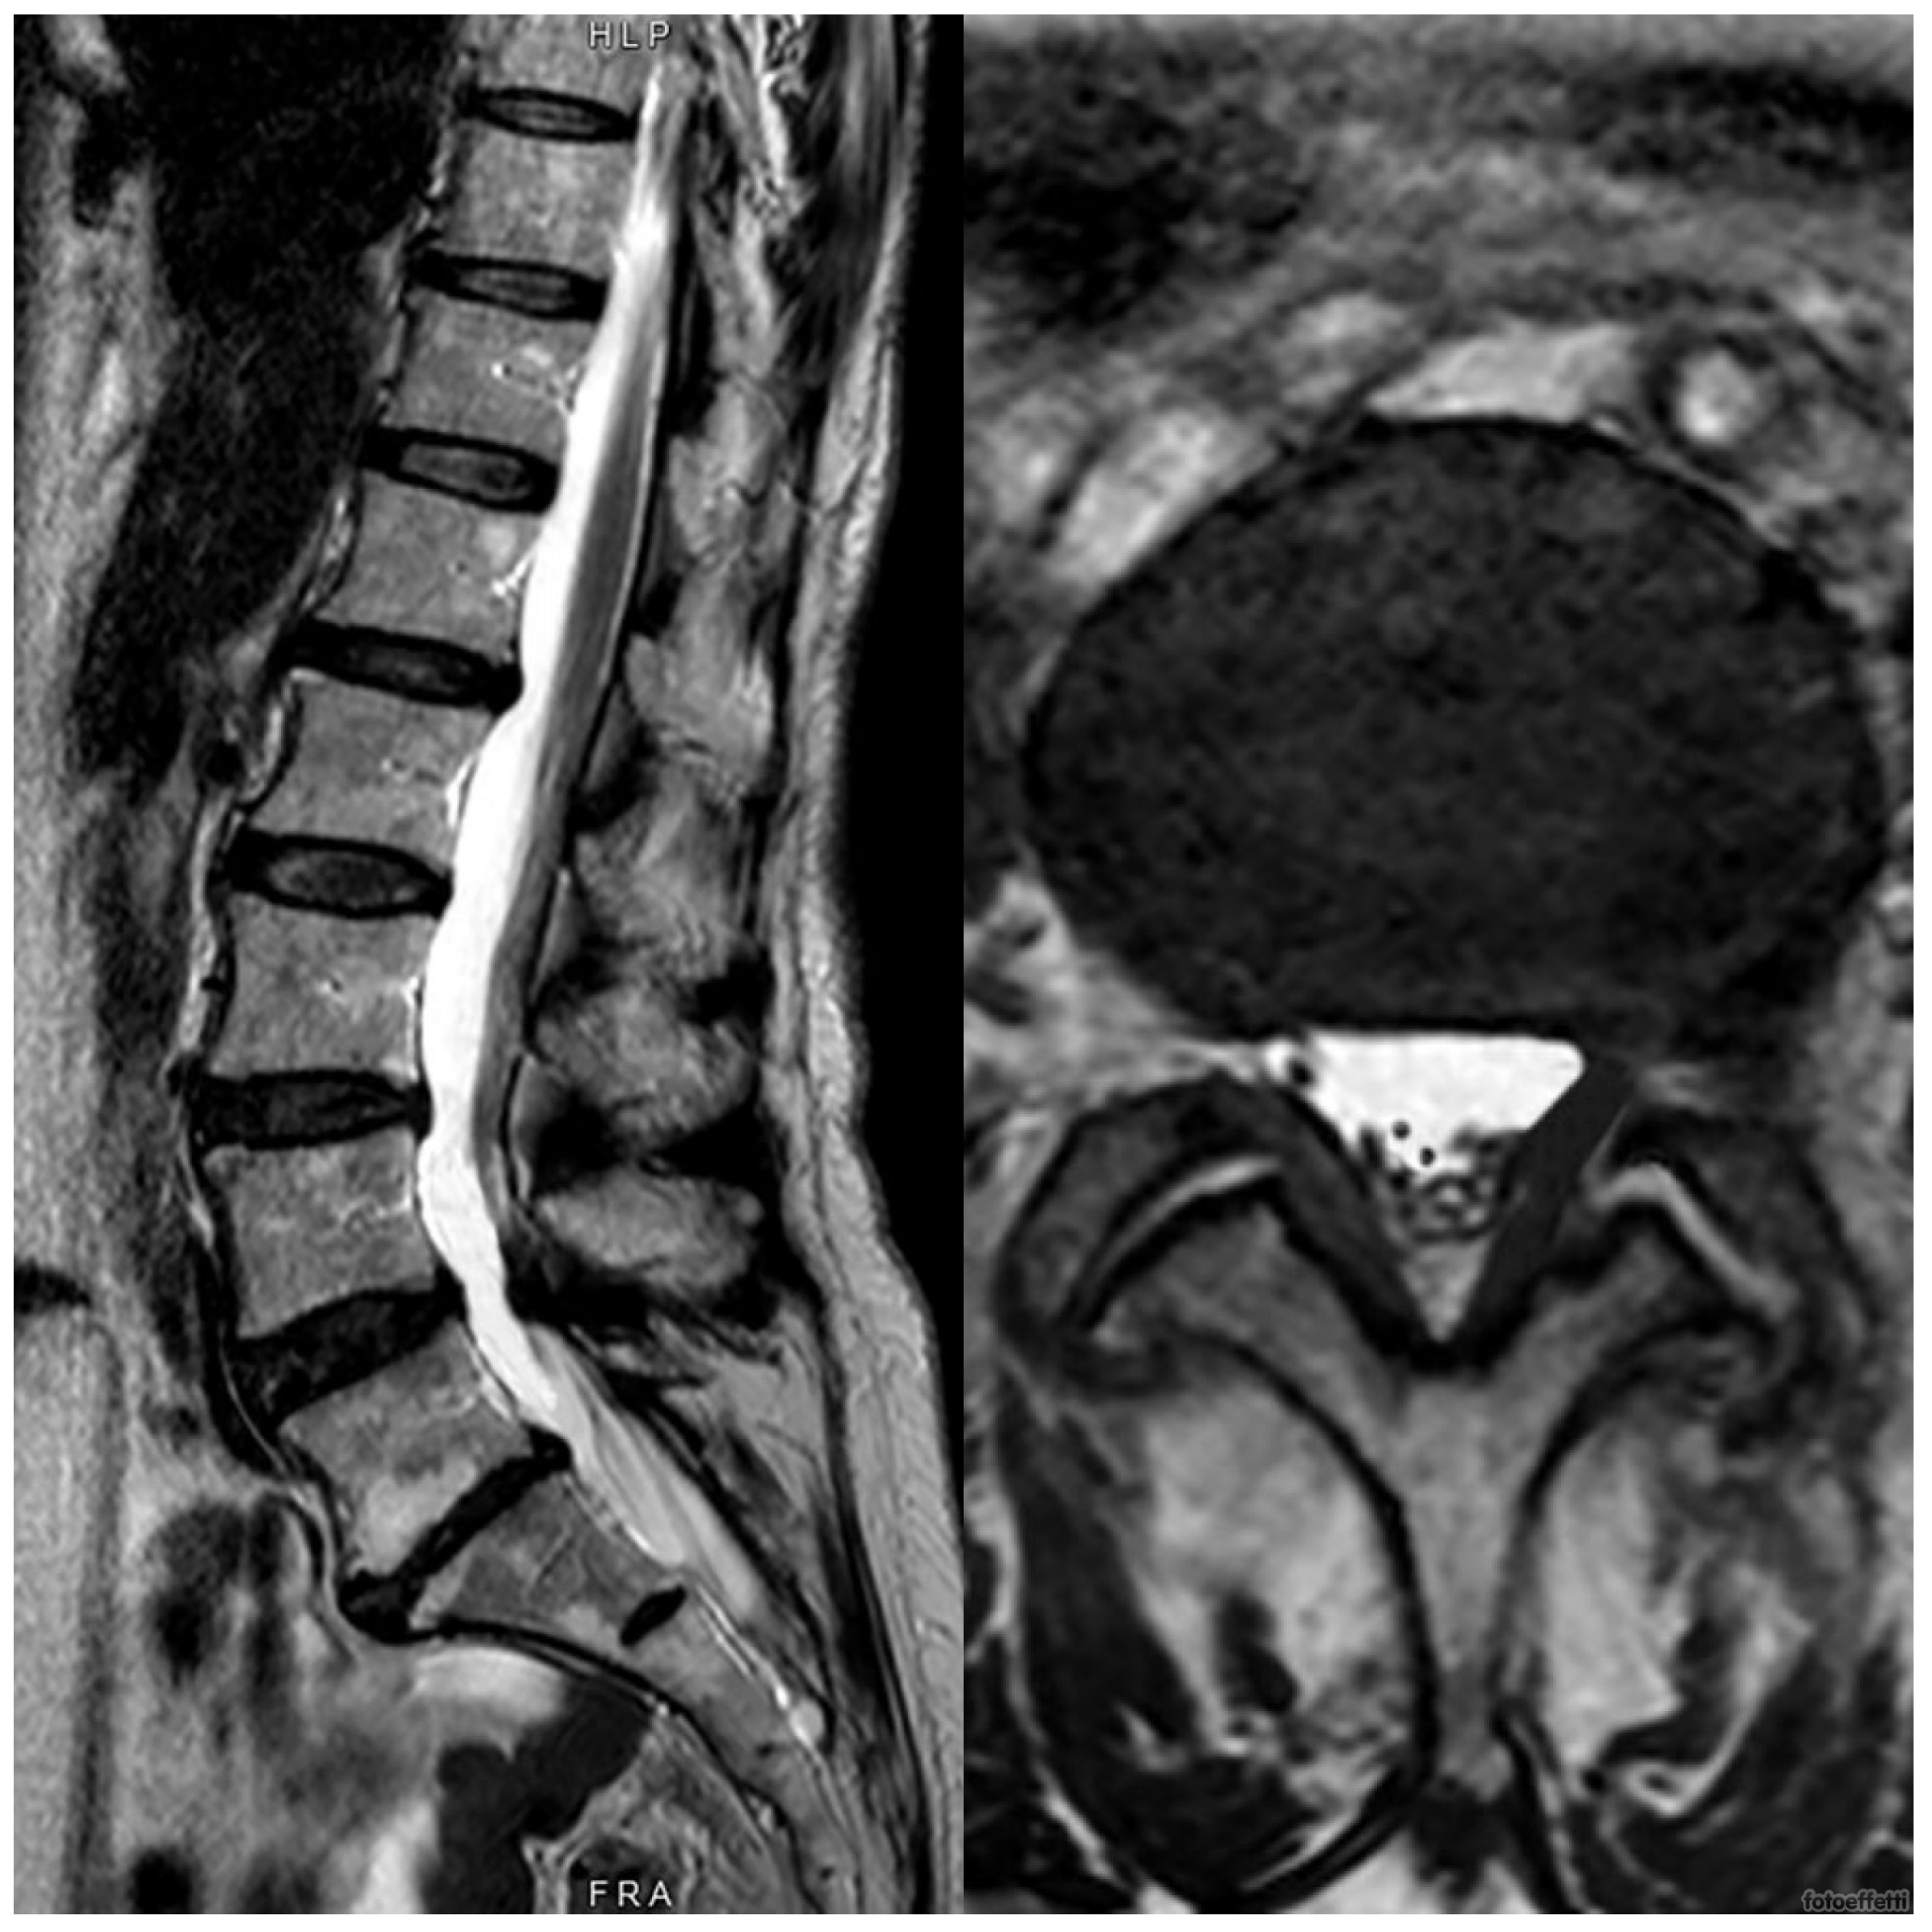

2. Case Presentation